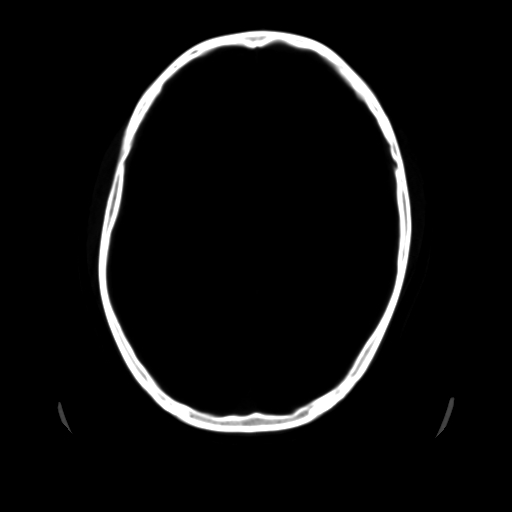

男,51岁,头外伤一小时,呕吐两次。

1)左侧中颅窝蝶骨翼后方硬膜外血肿。2)左侧颞顶部硬膜下血肿。3)蛛网膜下腔出血。4)左侧筛窦及双侧蝶窦炎症(或积血)。5)左侧额部头皮软组织肿胀。